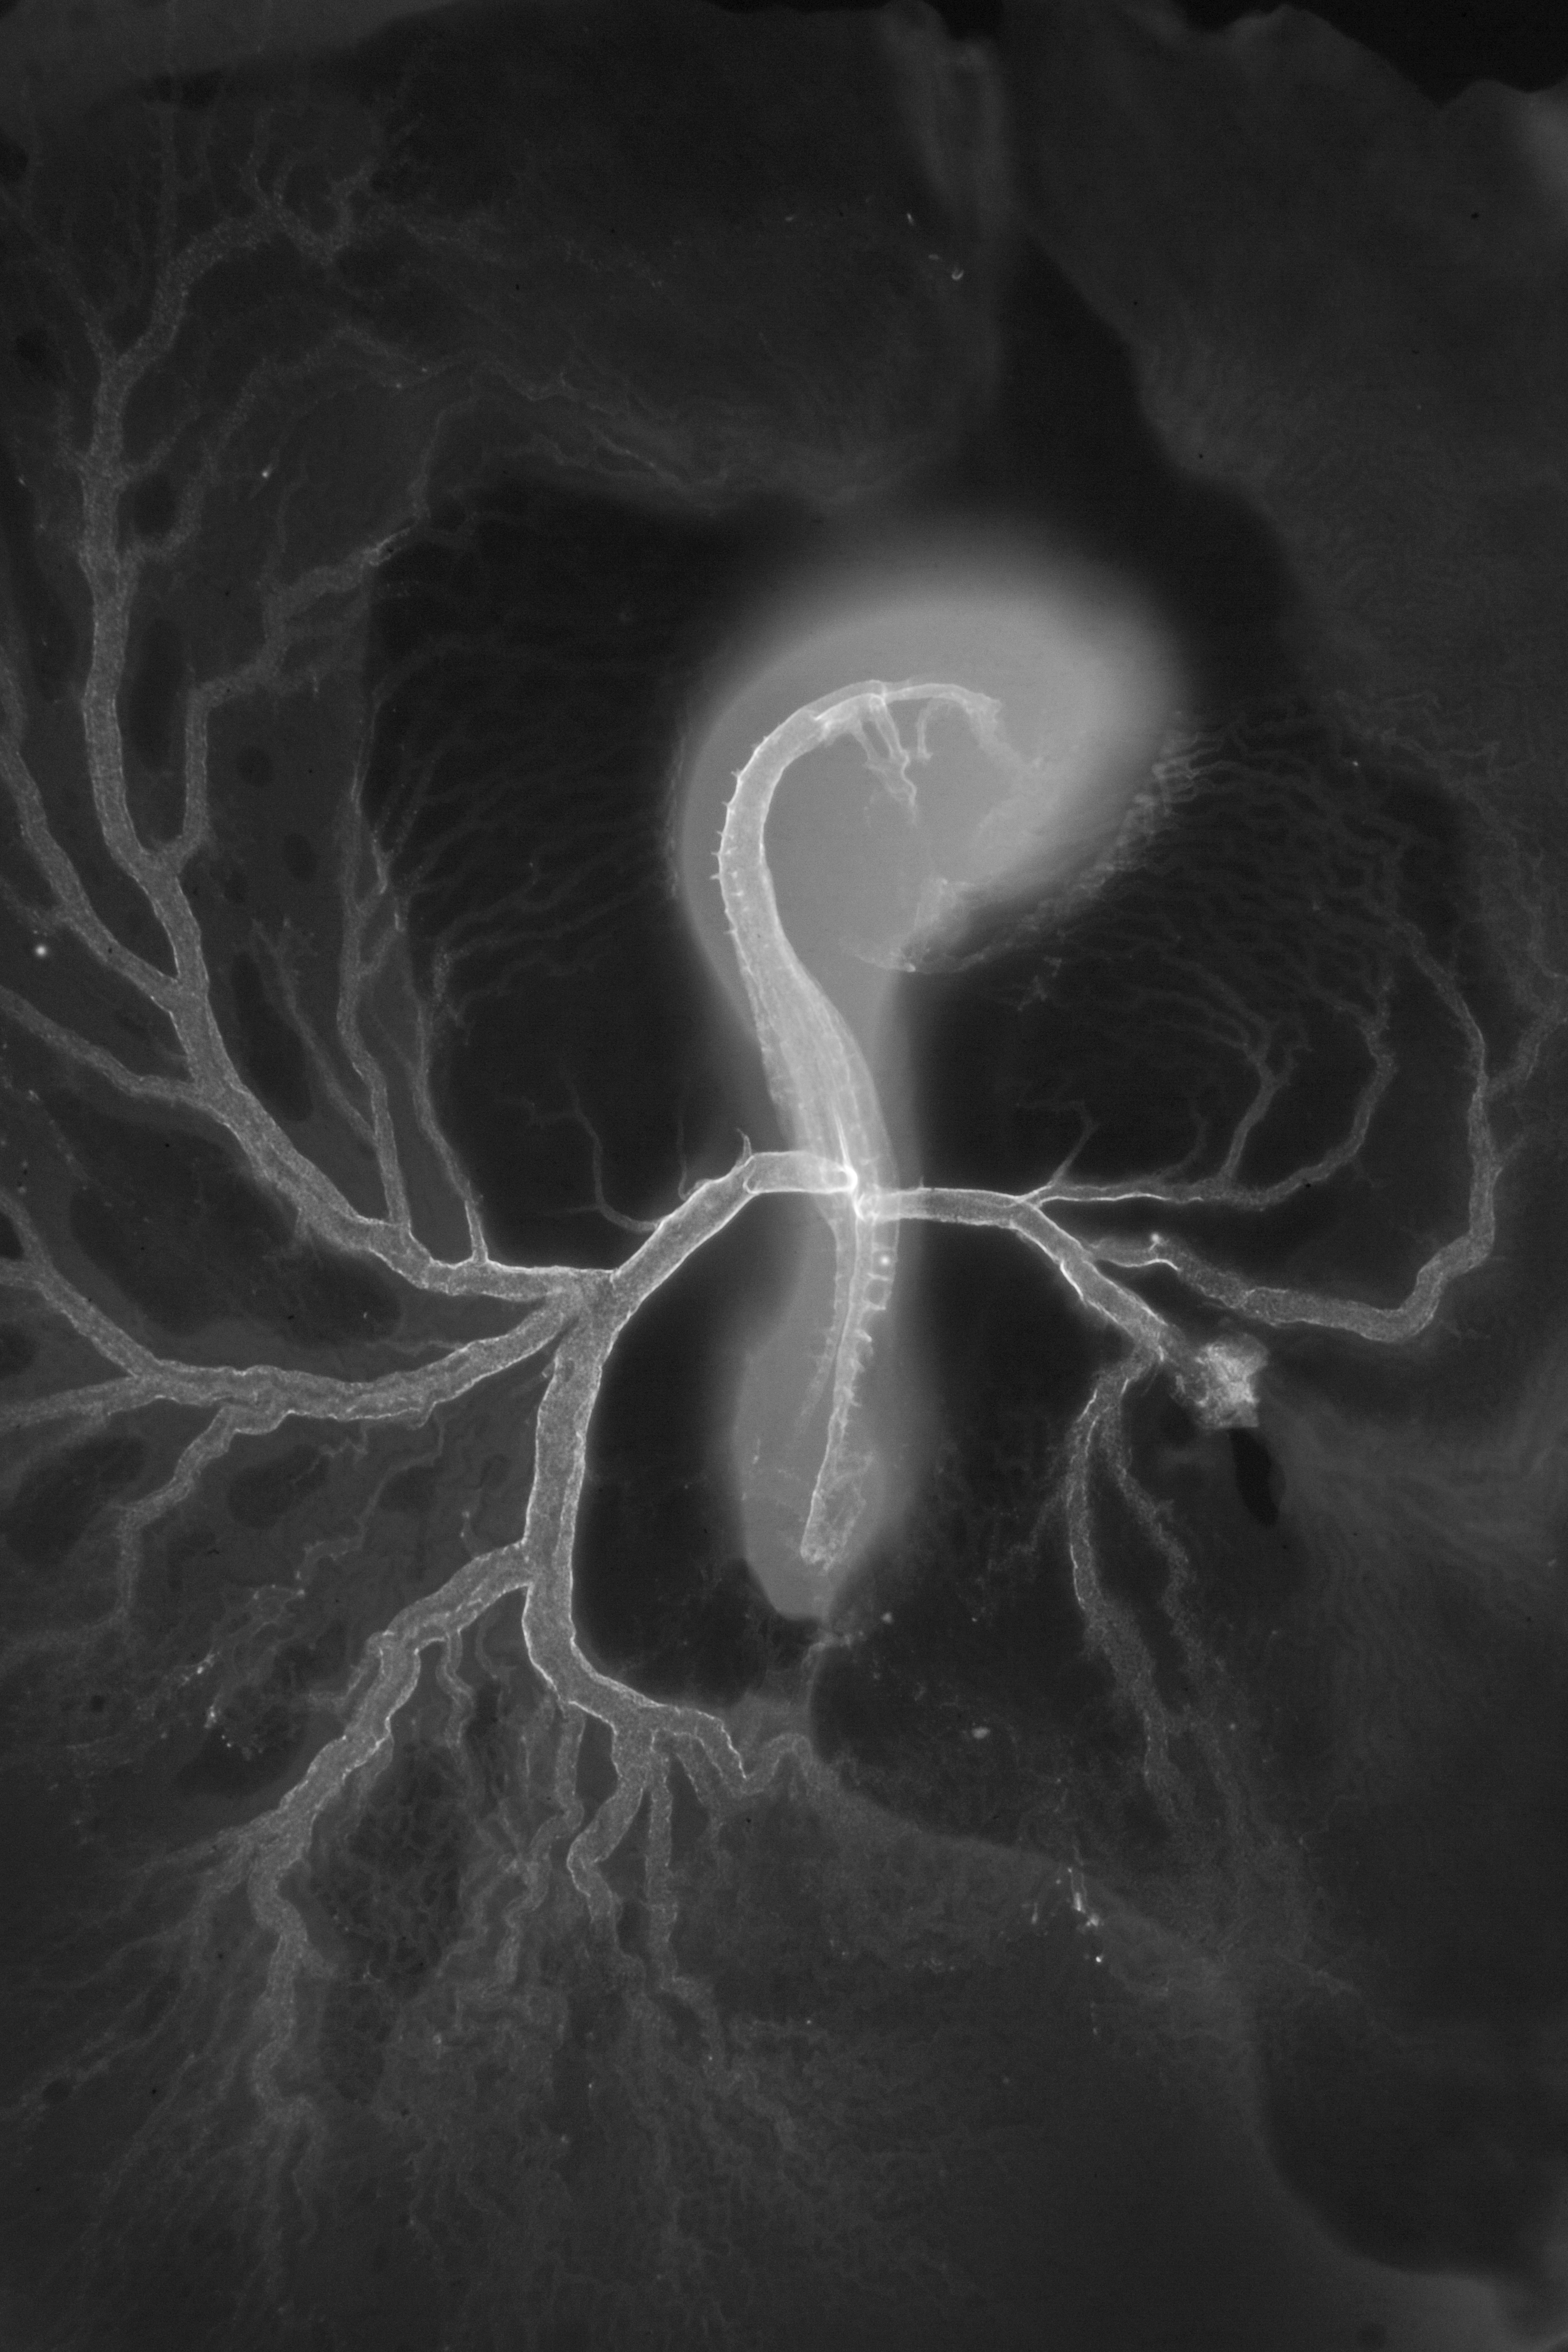

Chick Embryo Microangiography

Hamburger-Hamilton (HH) Stage 16 (approx. 2.1 - 2.5 days)

X-Ray Micrographs